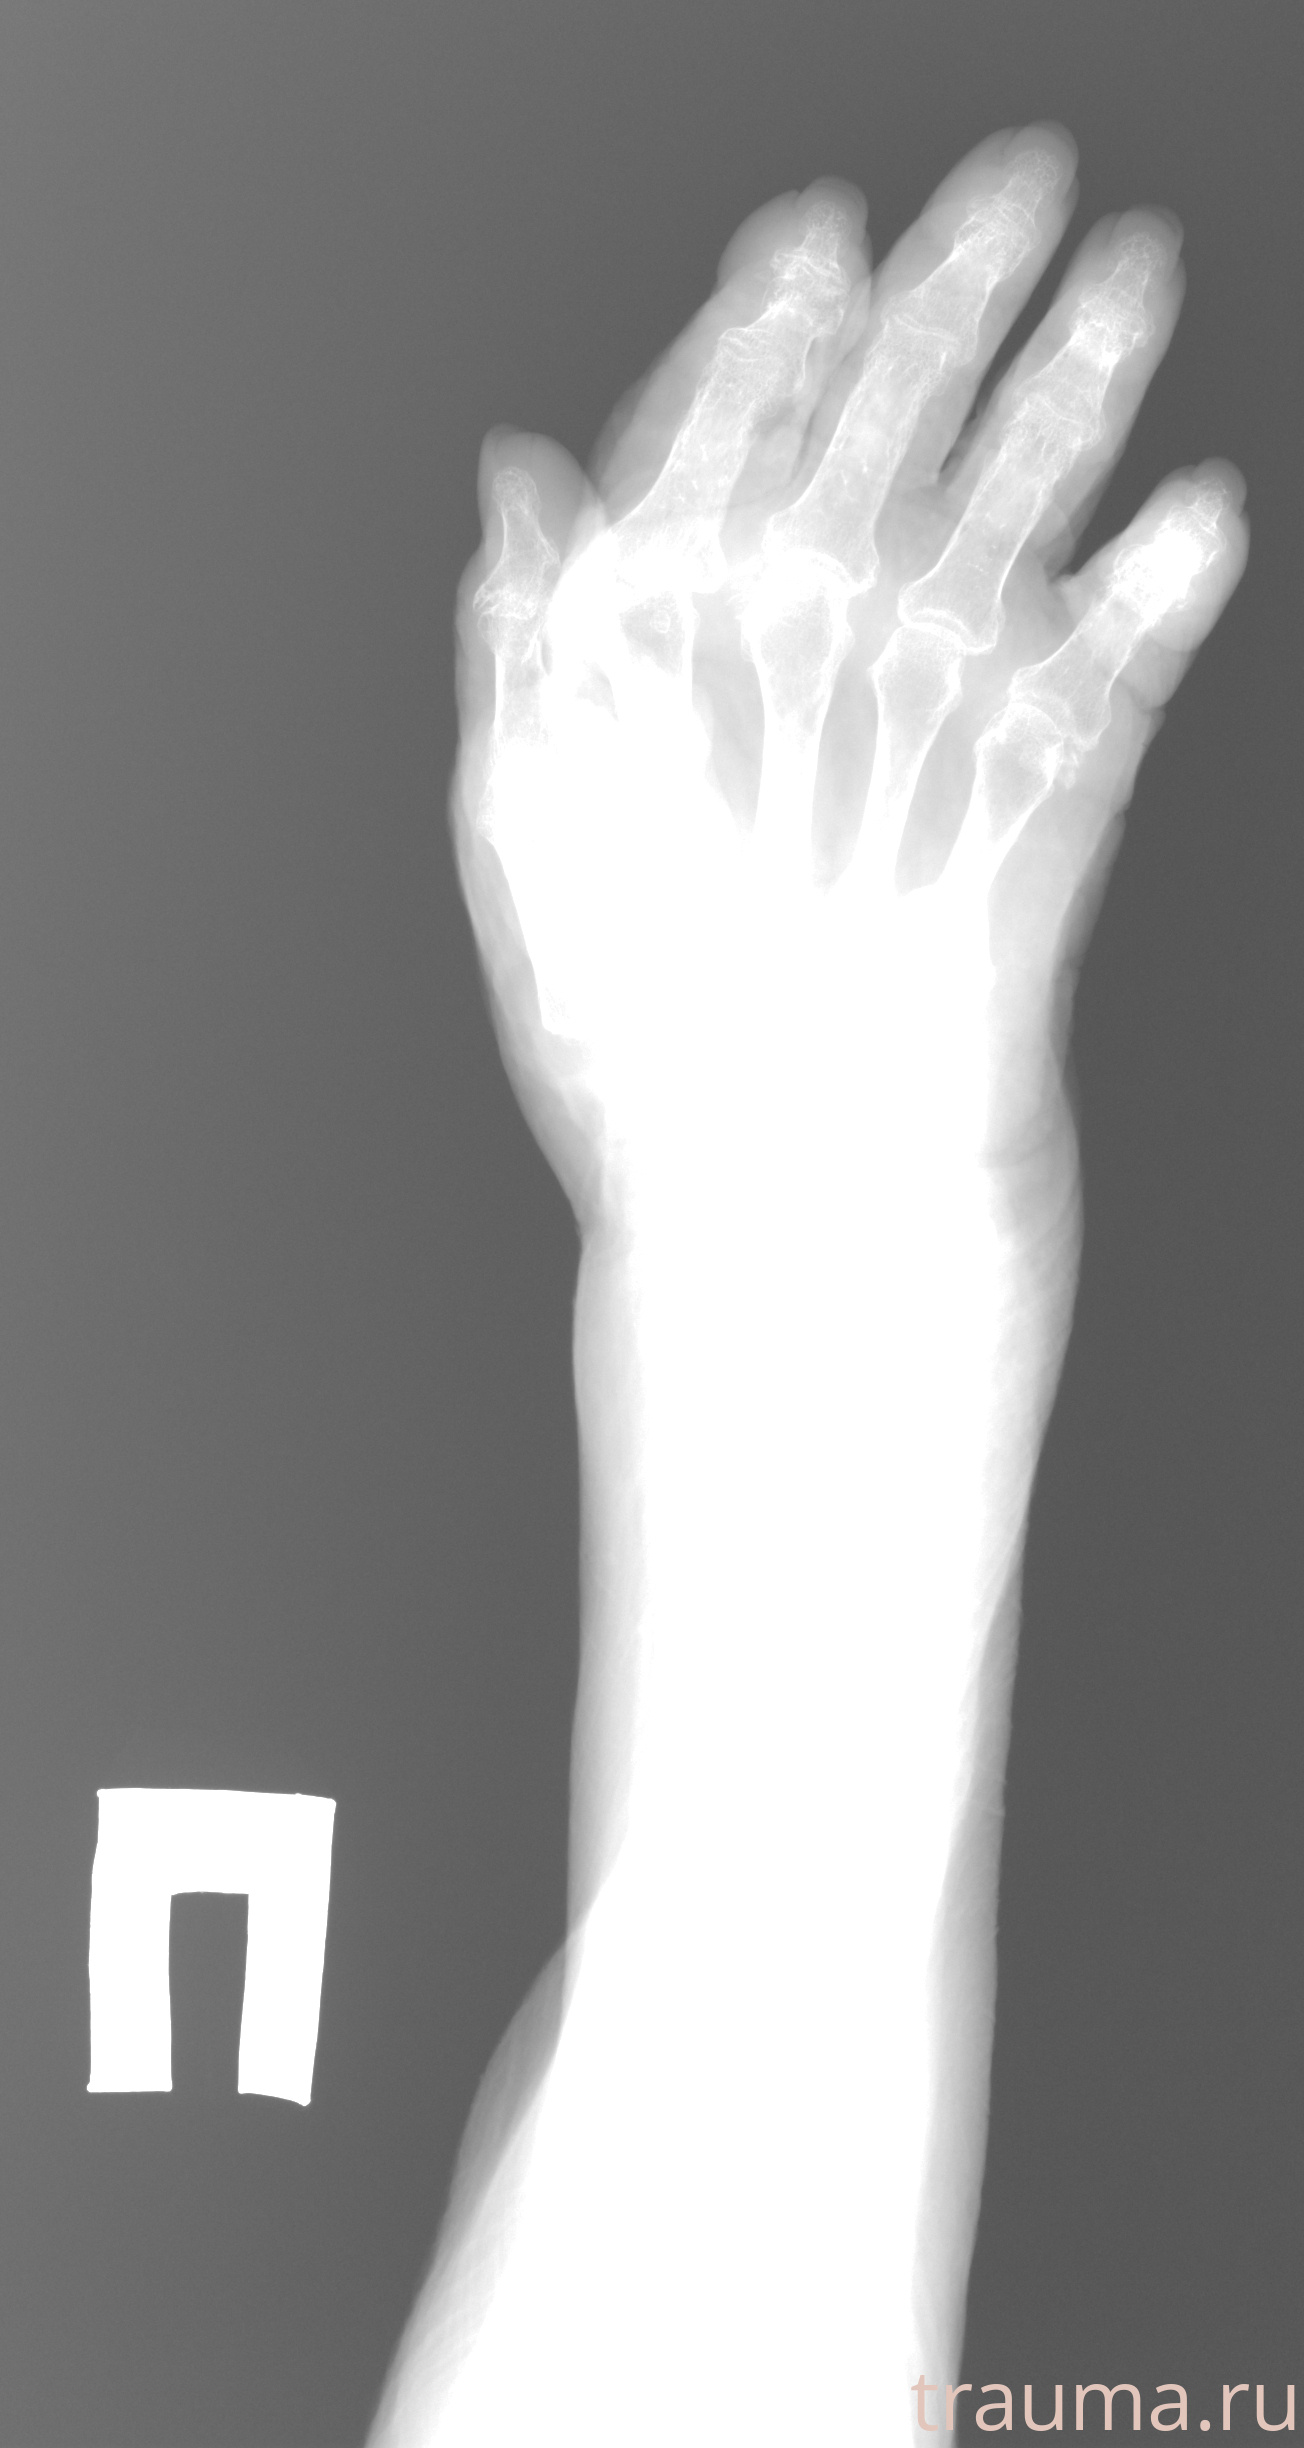

Рентген на дому: по вашему адресу приезжает врач-рентгенолог, травматолог-ортопед с мобильным рентгеновским аппаратом, проводит диагностику травмы или заболевания, делает необходимые рентгенограммы, дает рекомендации по дальнейшему лечению. Получить качественные снимки в домашних условиях возможно благодаря уникальной методике, разработанной МосРентген Центром для института  Склифосовского